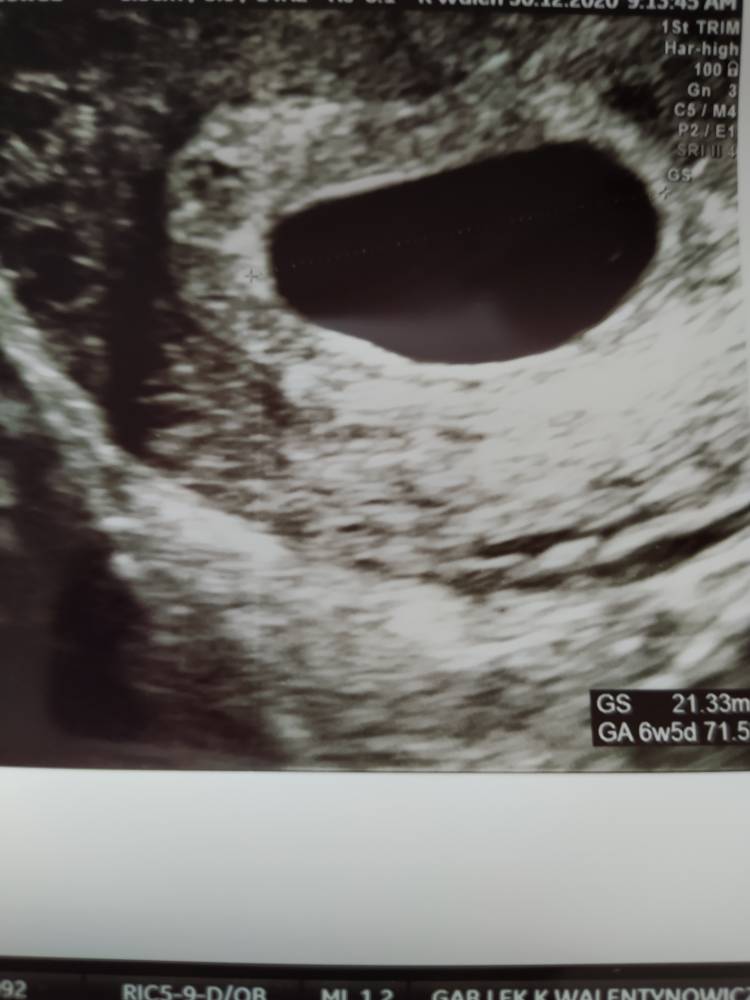

Dziś ta tragiczna wiadomość, ze jest pęcherzyk ciazowy ok. 20mm ale jest zupełnie pusty. Ani ciałka żółtego, ani zarodka. Za 5-6 dni kontrolne usg, ale skierowanie do szpitala już mam wystawione. Jestem załamana.

• IMG_20201230_100107.jpeg

49,6 KB · Wyświetleń: 2 954